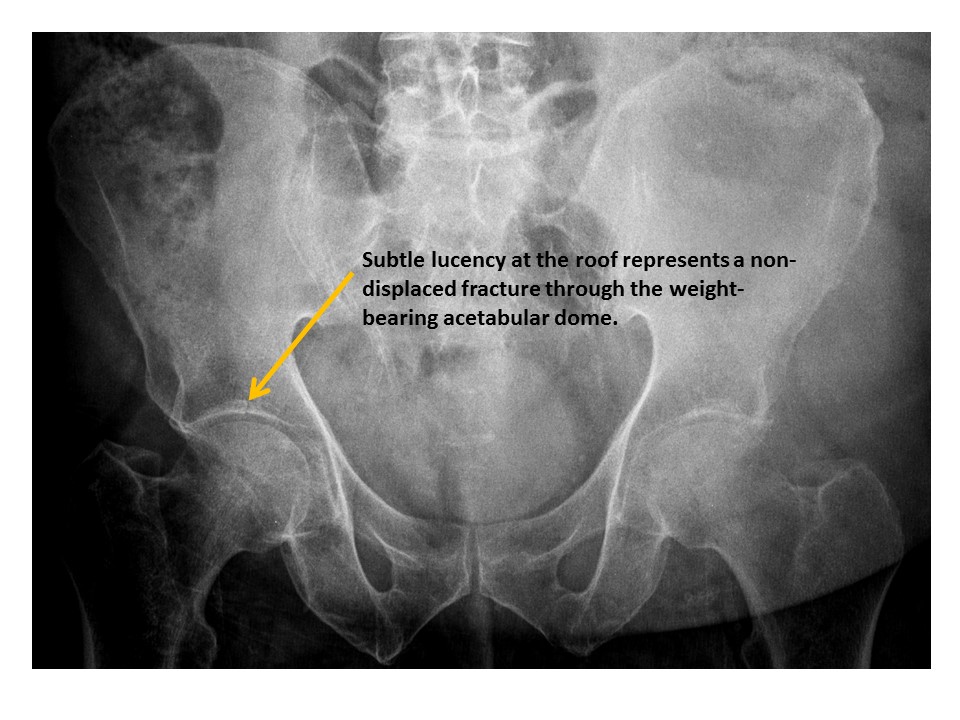

Acetabular roofs are discontinuous. [Yes/No]